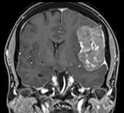

Ascesso

cerebrale |

Meningioma |